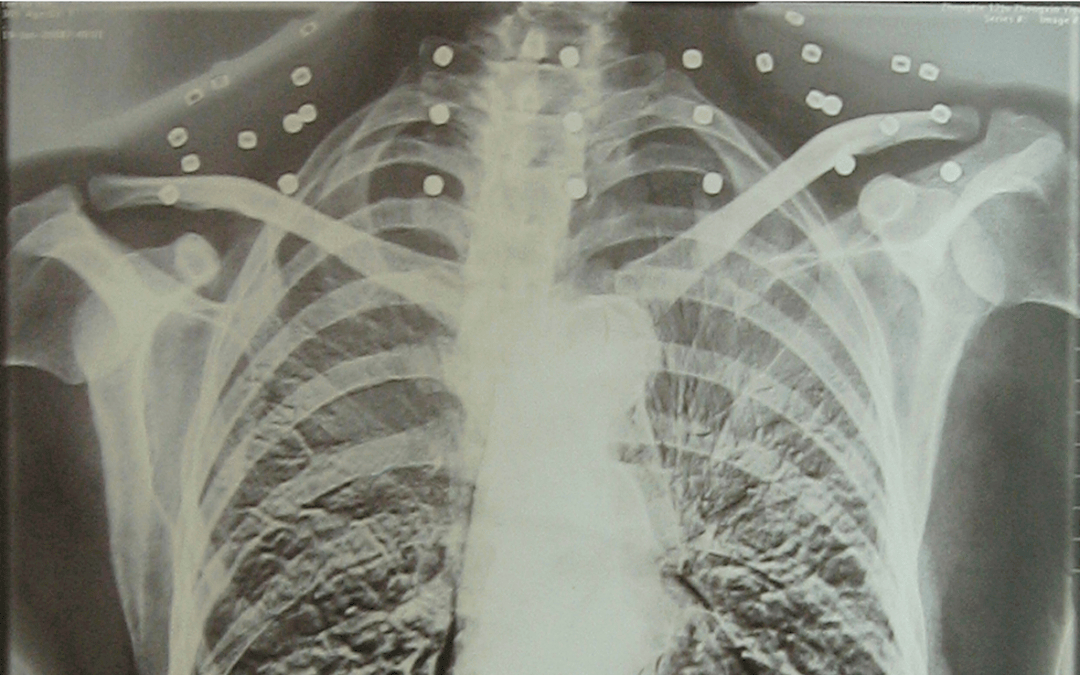

这张照片

是今年82岁的吴以先老人

拍摄的一张CT照

吴以先的颈部和腹部

共分布着33枚弹片

但是打进身体里的弹片

一直留在了体内

他体内的弹片都没有取出

与吴以先身上那33枚弹片